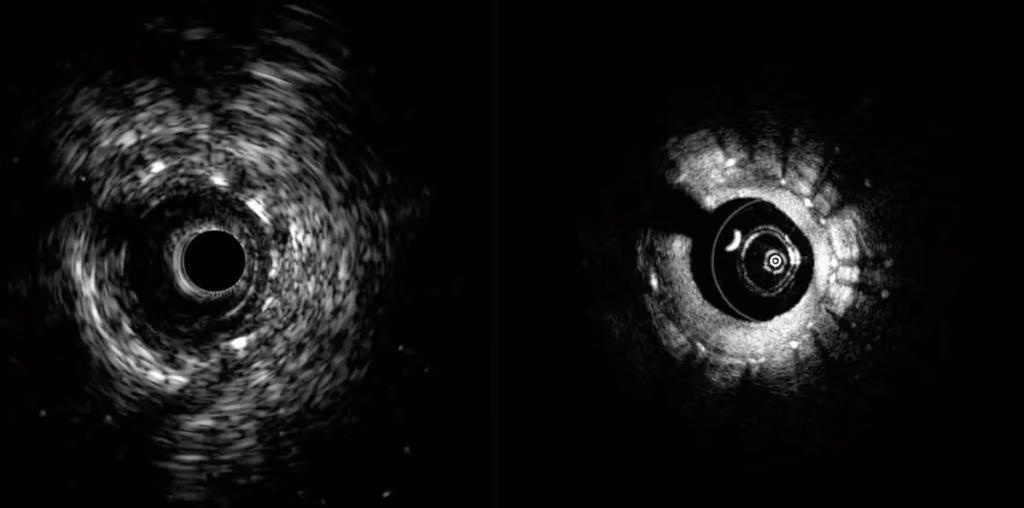

Conavi’s hybrid system integrates intravascular ultrasound (IVUS) and optical coherence tomography (OCT) in a single platform. Together, these technologies enable physicians to visualize both deep vessel structures and high-resolution surface detail in real time. The company says this supports physician decision-making and streamlines workflows.

According to Conavi, the system’s dual-modality approach can provide a comprehensive view of coronary arteries. This potentially enables more precise diagnosis and treatment of cardiovascular disease.